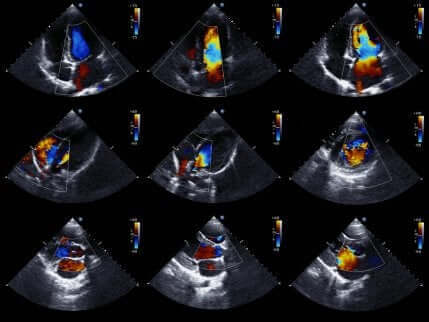

Avslutningsvis låter ultraljud läkarna studera hjärtat i mer detalj.

Ultraljud är ett väldigt populärt medicinskt test eftersom det ger rörliga bilder av hjärtat. Därmed kan det utvärdera statusen hos hjärtats kammare och deras rörelse för att bekräfta eller utesluta ischemi.

Det utvärderar även hjärtats storlek och styrka, såväl som tillståndet hos väggarna i hjärtkammarna.

Det är ett icke-invasivt test som inte involverar någon risk för patienten. Detta eftersom det använder ultraljud för att få hjärtbilder.

Om läkaren använder detta test så kan frånvaron av rörelsestörningar i hjärtväggen utesluta närvaron av ischemi. Närvaron av rörelsestörningar är trots allt inte ett unikt symptom för akut kranskärlssjukdom.

Därför måste de olika testresultaten utvärderas tillsammans.